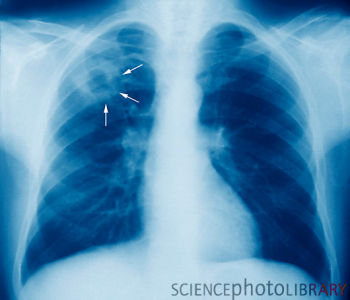

La tuberculosis es la principal causa de muerte entre las enfermedades infecciosas en el mundo y es responsable de uno de cada cuatro muertes evitables de adultos, según la Organización Mundial de la Salud (OMS). Cada TB 20 segundos mata a alguien, con aproximadamente 4.400 personas que mueren todos los días. La OMS estima que un tercio de la población mundial está infectada.

bacterias que esta escondidas en el cuerpo